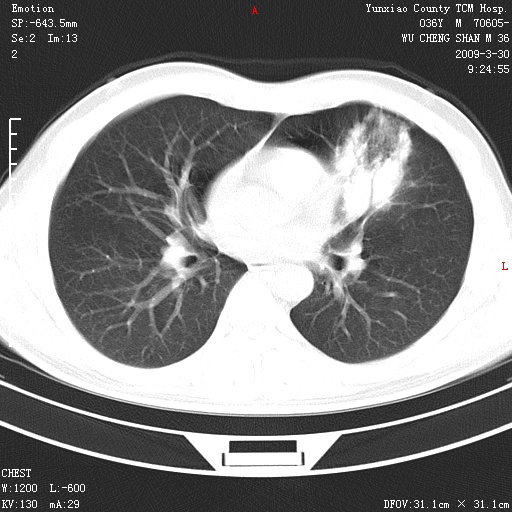

本院家属,胸痛,无咳嗽咳痰发烧病史,治疗一个月后病灶无明显改变,支气管镜示左肺慢性炎症,未见癌细胞,

胸痛,无咳嗽咳痰发烧病史,治疗一个月后病灶无明显改变,支气管镜示左肺慢性炎症,未见癌细胞,左肺下叶前段片状影,边缘不清,内见空支气管征,纵隔未见淋巴结肿大,周围无卫星灶,应考虑为炎性病变。

胸痛,无咳嗽咳痰发烧病史,治疗一个月后病灶无明显改变,支气管镜示左肺慢性炎症,未见癌细胞,左肺舌叶片状影,边缘不清,内见空支气管征,周围无卫星灶,应考虑为炎性病变。

左肺舌叶片状影,边缘不清,内见空支气管征,炎性病变